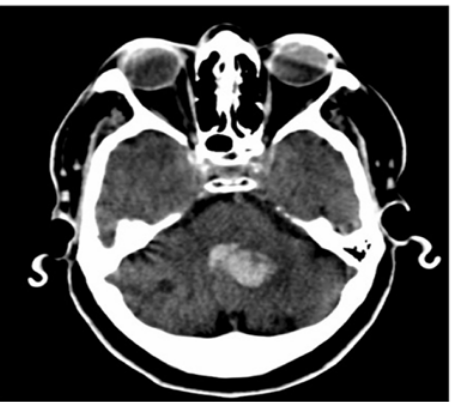

AVC hémorragique sur angiopathie hypertensive

Publié par : Dr. emile barracois